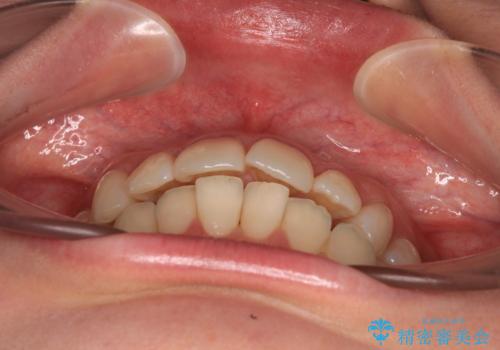

上下前歯のデコボコ ワイヤー装置で楽ちん矯正治療

- 前歯のデコボコや、やや突出した感じを気にして来院された患者様です。

抜歯矯正を必要とするほど口元の突出感はなく、本人もそこまでは気にしていない様子でした。

矯正治療後には奥歯の銀歯やむし歯をセラミックやゴールドにて治療を行い、大変整った口腔環境へと改善さ。れました